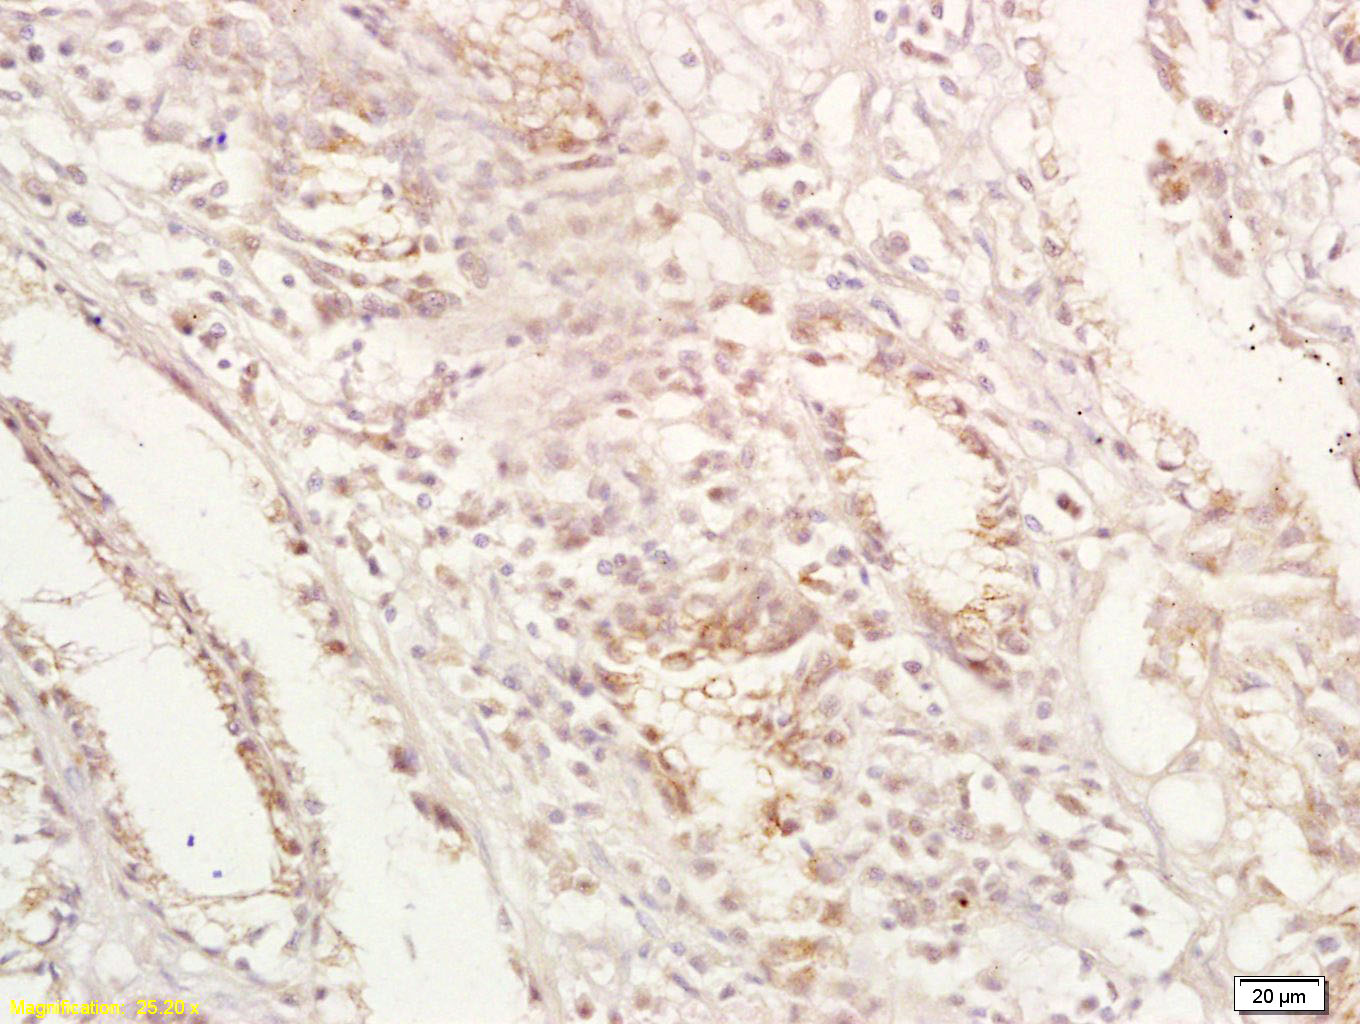

Paraformaldehyde-fixed, paraffin embedded (human colon carcinoma); Antigen retrieval by boiling in sodium citrate buffer (pH6.0) for 15min; Block endogenous peroxidase by 3% hydrogen peroxide for 20 minutes; Blocking buffer (normal goat serum) at 37°C for 30min; Antibody incubation with (GPA33) Polyclonal Antibody, Unconjugated (bs-1226R) at 1:400 overnight at 4°C, followed by operating according to SP Kit(Rabbit) (sp-0023) instructionsand DAB staining.